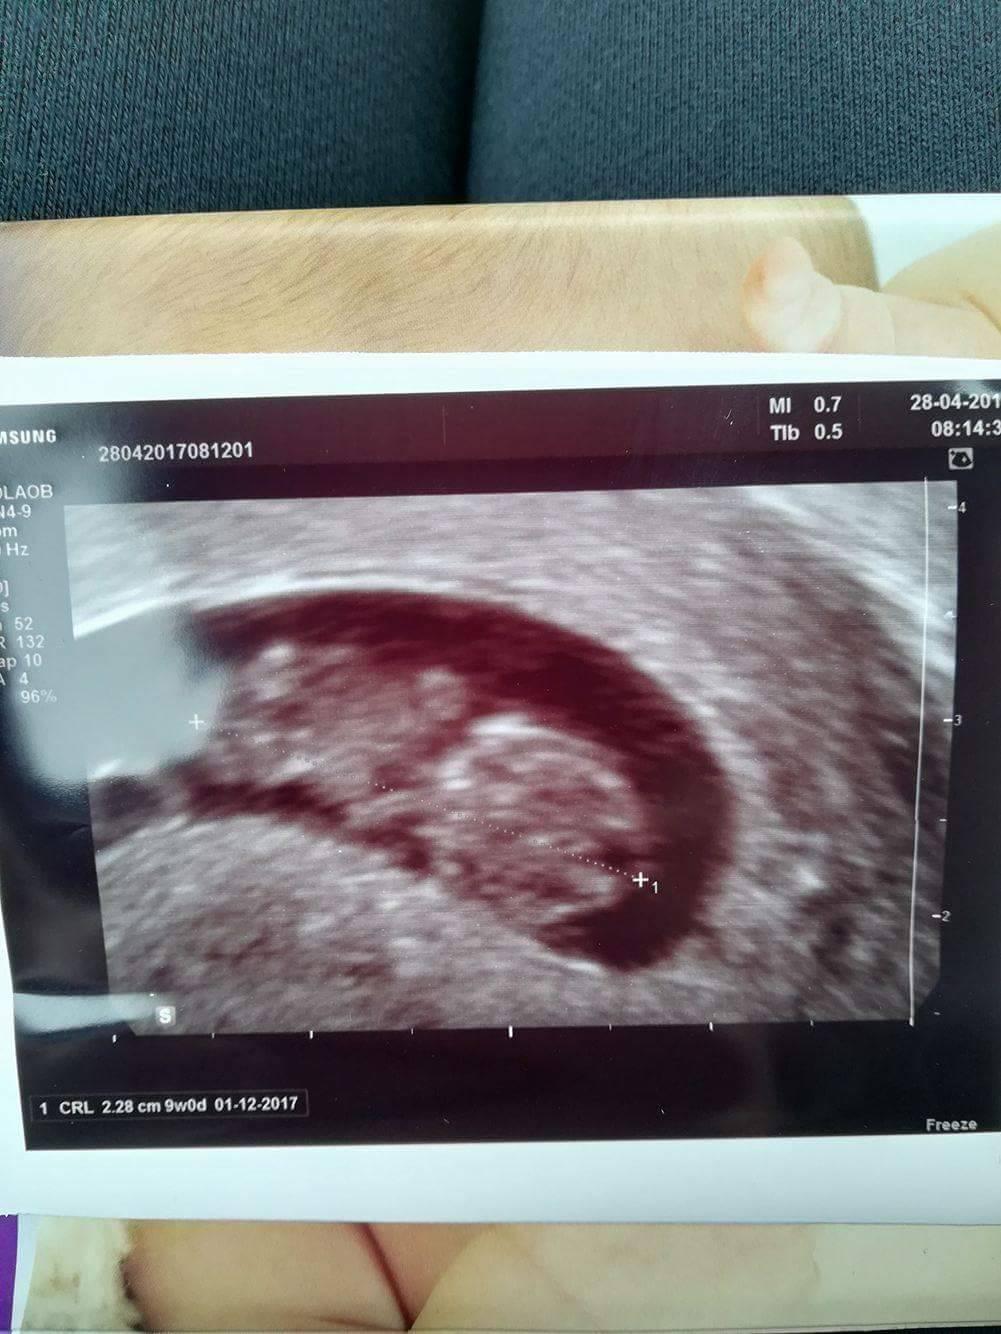

takze pridam ultravuk ktory bol robeny 28.4.2017 a v lavom rohu dole je napisane datum 1.12.2017 a hned za tym 9w0d

to znamena ze bola v 9 tyzdni?ako priblizne vypocitat kedy otehotnela?od toho snimku odratat 9 tyzdnov dakujem velmi pekne.

Ak je v 9. Týždni, tak mohla otehotnieť cca pred 7 týždňami